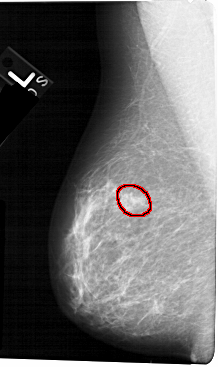

A_1323_1.LEFT_CC

LEFT_CC LINES 5296 PIXELS_PER_LINE 2896 BITS_PER_PIXEL 12 RESOLUTION 43.5 OVERLAY

FILE: A_1323_1.LEFT_CC.OVERLAY

TOTAL_ABNORMALITIES 1

ABNORMALITY 1

LESION_TYPE MASS SHAPE OVAL MARGINS OBSCURED-ILL_DEFINED

ASSESSMENT 4

SUBTLETY 2

PATHOLOGY BENIGN

TOTAL_OUTLINES 1

BOUNDARY